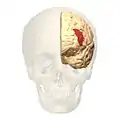

Brodmann area 46, or BA46, is part of the frontal cortex in the human brain. It is between BA10 and BA45.

BA46 is known as middle frontal area 46. In the human brain it occupies approximately the middle third of the middle frontal gyrus and the most rostral portion of the inferior frontal gyrus. Brodmann area 46 roughly corresponds with the dorsolateral prefrontal cortex (DLPFC), although the borders of area 46 are based on cytoarchitecture rather than function. The DLPFC also encompasses part of granular frontal area 9, directly adjacent on the dorsal surface of the cortex.

Lateral view.